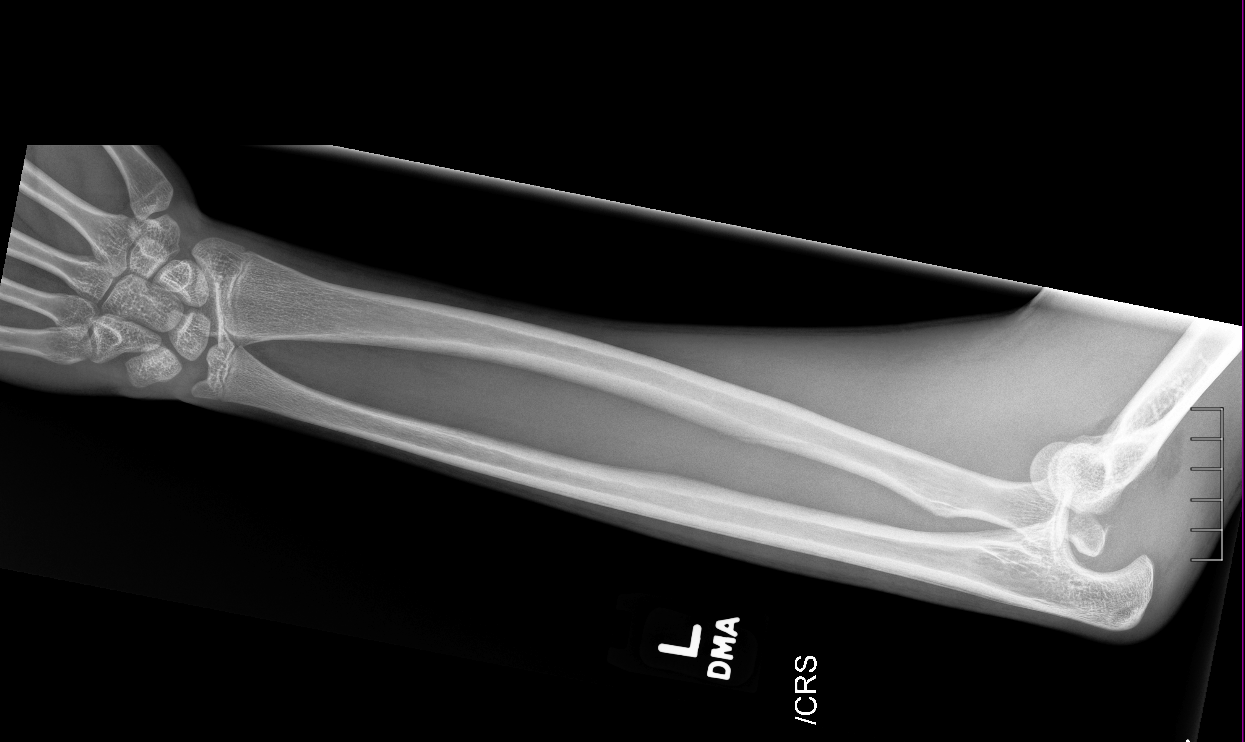

Info Images Findings Impression Reco/Acuity Case Images View Images / Launch Visage Case Notes History 2-month-old presents with decreased right arm movement, increased fussiness, and increased sleepiness for 2 days. Suspected non-accidental trauma. Exam Skeletal survey Prior Study none Dicom View Reference Material

Section 1 Submit Findings CB1550 Findings Skeletal Survey - Technique Check Skull AP/Lat Yes No Cervical and Thoracolumbar spine Yes No Chest X-Ray Yes No Ribs – Left/Right Oblique Yes No Abdominal X-Ray Yes No Pelvis with both hips Yes No Bilateral Humerus, Forearm, Hand Yes No Bilateral Femur, Tibia/fibula, feet Yes No Any additional lateral views of the extremities Yes No The exam is over or under penetrated. Yes No The exam may or may not be limited by overlying structures or soft tissues, body habitus, patient positioning, support devices, or motion. Yes No The area of concern is indicated by the patient, technologist, or care provider. Yes No The area of concern is included on the exam. Yes No Soft Tissues There is soft tissue swelling, indistinctness of fat/muscle planes, gas, or laceration in the area of clinical concern. Yes No There is an effusion, fat pad displacement, or fat fluid level. Yes No There is a radiodense or lucent foreign body. Yes No There are other densities, calcifications, post-surgical changes, or support devices in the soft tissues. Yes No Any support lines/tubes. Yes No Bone There is a break or interruption of the continuity of the cortical or cancellous bone. Yes No There is overriding of the trabeculae with apparent sclerosis. Yes No There is displacement of a fracture fragment. Yes No There is bowing of the bone in addition to the fracture at the apex of the bowed bone concerning for the greenstick. Yes No There is a spiral fracture of the leg concerning for toddler’s fracture. Yes No There is abnormal angulation or bulging of the cortical surface relative to the normal cortex which could be from a buckle or torus fracture. Yes No There is a displaced fragment which may be from avulsion by a tendon, ligament, or joint capsule or from a comminuted or other fracture. Yes No The stress trabeculae or other trabeculae of the cancellous bone are interrupted or otherwise abnormal. Yes No There is subperiosteal or endosteal reaction which could indicate a healing or subacute fracture or other abnormality. Yes No There is hard/soft callus formation. Yes No There is remodeling of the bone. Yes No There is a corner fracture or metaphyseal lesion that could be from nonaccidental trauma. Yes No There are multiple fractures of different ages. Yes No There are vertebral body/spinous process fractures. Yes No There are rib fractures. Location - posterior or lateral. Yes No There is scapular/sternal fracture. Yes No There are fractures of the digits. Yes No There are wormian bones. Yes No There are intrasutural bones. Yes No There is metaphyseal abnormality (lucencies, increased density, erosion) which may be from something other than injury such as stress, metabolic disease (e.g. rickets with loss or distortion of the zone of the provisional calcification), neoplasm (e.g. leukemia), heavy metals, inflammation, or infection. Yes No There are metaphyseal spurs. Yes No There are bony deformities involving multiple bones. Yes No The bones are gracile. Yes No There are non-healing fractures. Yes No There is/are focal or multifocal lytic/lucent, blastic/sclerotic or mixed density lesion(s) or other abnormality. Yes No Overall bone density is increased or decreased with or without thinning or thickening of the cortical or cancellous bone. Yes No Growth plates, ossification centers, apophyses The growth plate(s) is/are abnormal. Yes No There is widening of the physis from a fracture with or without displacement of the epiphysis (Salter-Harris I). Yes No There is a fracture through the physis which then extends into the metaphysis with or without angulation or displacement (S-H II). Yes No There is a fracture through the physis which then extends into the epiphysis and is intra-articular, with or without angulation or displacement (S-H III). Yes No There is a fracture through the metaphysis, physis, and epiphysis which extends into the joint space with or without angulation or displacement (S-H IV). Yes No There is narrowing of the physis from a compression fracture (S-H V). Yes No The apophysis, epicondyle, secondary ossification center, or accessory ossicle is displaced or otherwise abnormal. Yes No The ossification centers are underdeveloped. Yes No Joints and alignment There is an effusion, fat pad displacement, or fat fluid level. Yes No The epiphysis or subchondral bone is fractured, interrupted, flattened, compressed, impacted, displaced, or otherwise abnormal. Yes No There is an intra-articular loose body or chondrocalcinosis. Yes No The joint is widened, narrowed, dislocated, malaligned, or incongruent. Yes No There is pseudoarthrosis. Yes No Other findings There are developmental changes or other anatomic variants or other existing conditions that may or may not be contributing to symptoms which can or should be further evaluated non-emergently or are otherwise incidental. Yes No The remainder of the exam is abnormal for age. Yes No The lungs show focal airspace opacity. Yes No There is pneumothorax. Yes No There is organomegaly. Yes No There is intra-abdominal calcification. Yes No There is displacement of the bowel loops. Yes No There is free intraperitoneal air. Yes No The bowel loops are dilated/obstructed. Yes No There is paraspinal soft tissue abnormality. Yes No